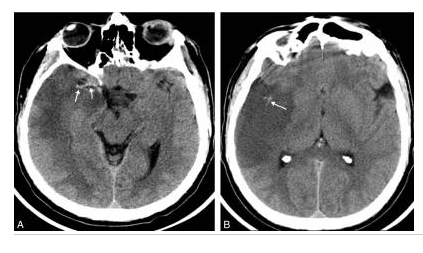

Hématome profond chez un patient âgé hypertendu en scanner.

Coupe axiale sans injection de produit de contraste iodé : hyperdensité spontanée (astérisque) de la région des noyaux gris centraux. Rupture de cet hématome dans le carrefour ventriculaire droit entraînant une hémorragie intraventriculaire avec dilatation ventriculaire (flèches). Pas d’indication à la réalisation d’explorations vasculaires complémentaires.